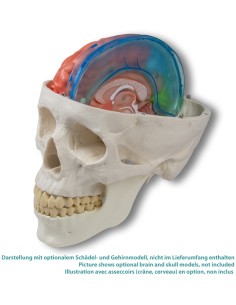

Crâne classique transparent, séparable en 3 parties, modèle anatomique 3B Scientific A20/T

Crâne avec gnathoschisis et fente palatine, modèle 3B Scientific A29/3

3B scientifique, enseignement de luxe crâne BONElike™A283